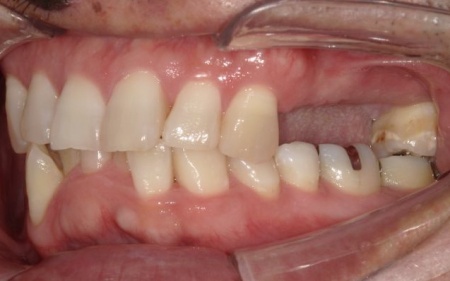

患者様は「可能な限り自分の歯を残したい」と希望されており、長期的な安定と清掃のしやすさを考慮して、②のインプラントブリッジによる治療を選択されました。

感染が周囲に広がらないよう配慮しながら、慎重に抜歯を行いました。

抜歯後は骨や歯茎の回復を待ち、口腔内の状態が安定した段階で、インプラント埋入手術へ進みました。

インプラントは、右上4番目と6番目の位置、左上4番目と6番目の位置に埋め込みます。

インプラントがしっかりと骨に定着したことを確認したら、精密な型取りを行い、ブリッジを作製して装着しました。

インプラント治療と併せて保存可能な歯の治療も進め、右上の一番奥の歯と右下の奥歯(前から5番目と6番目)に対して、細菌感染した神経を取り除いてから薬を詰める根管治療を行い、CAD/CAM冠という白い被せ物で修復しました。

さらに、上前歯(右上の犬歯から左上の犬歯まで)、右下の4番目の歯に対しては、虫歯治療を行っています。

最後に、痛みや違和感がないか、見た目や噛み合わせに問題がないかを確認し、治療を終了しました。